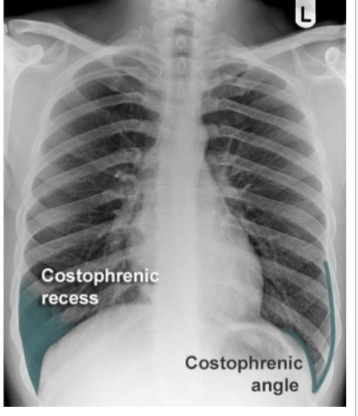

identify costophrenic angles

yes